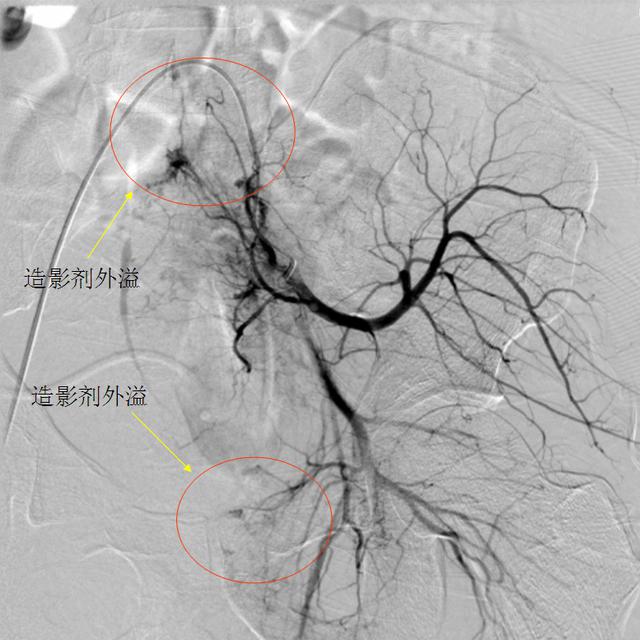

穿刺、送导丝、进导管,造影,时间一分一秒过去,出血点终于找到了!左侧髂内动脉分支血管,可见多处造影剂外溢征象。

在微导管引导下,医师用明胶海绵颗粒依次对全部出血动脉进行了栓塞。